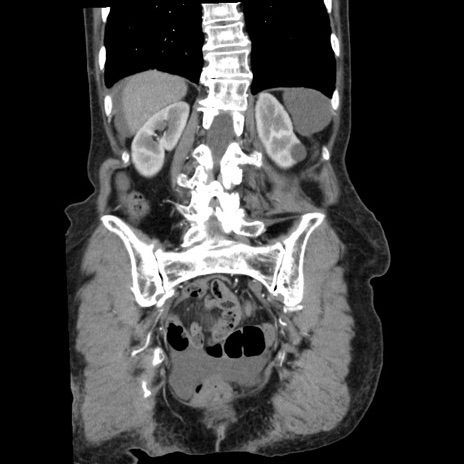

症例1(冠状断像)

症例

【症例】80歳代女性

【主訴】腹痛

【現病歴】8時間前から腹痛あり来院。

【既往歴】糖尿病、脂質異常症、子宮体癌にて子宮全摘術

【身体所見】意識清明・会話良好だが腹痛で苦悶様、全腹部にわたって反跳痛と圧痛あり

【データ】WBC 13600、CRP 0.14、LDH 224、CK 90